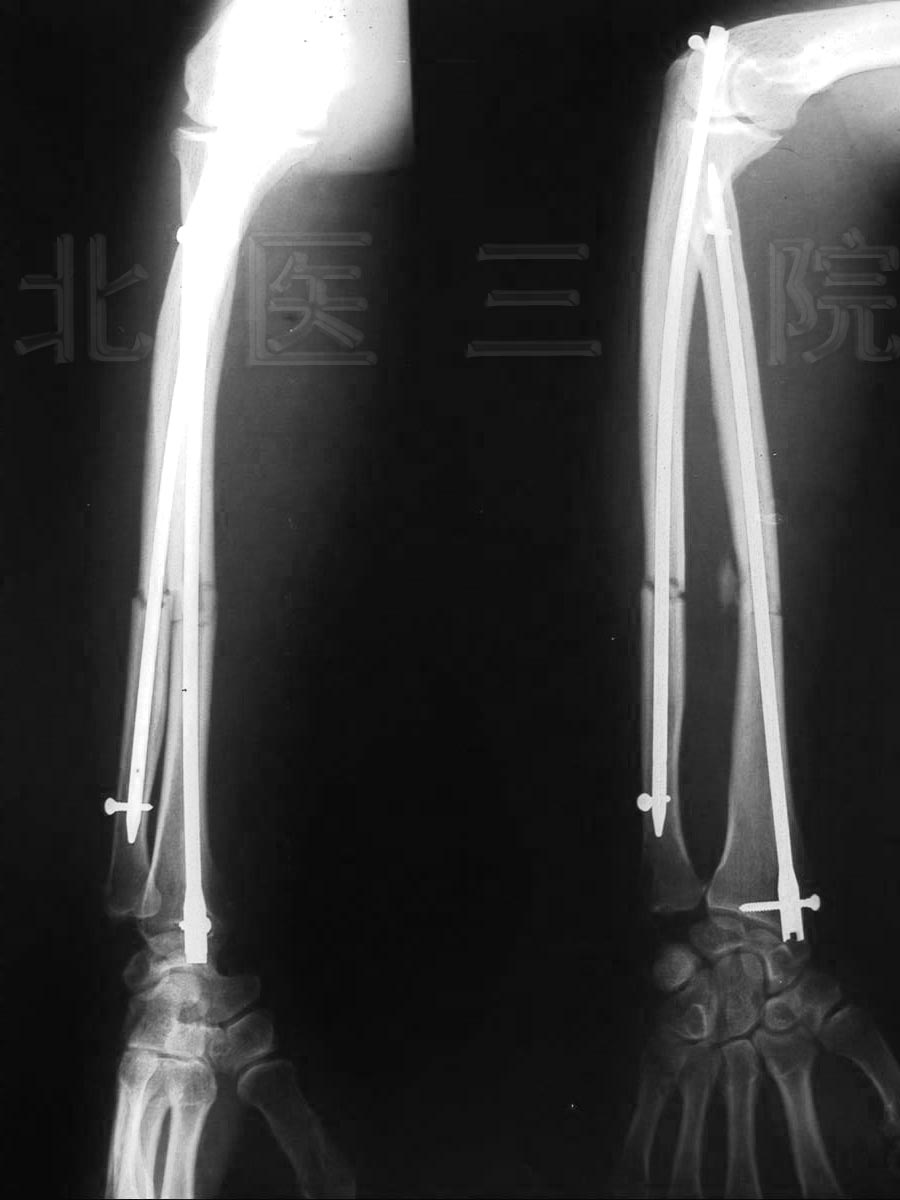

图1:肱骨干骨折11年不愈合,外院4次手术,患者左上臂存在异常活动。

FIGURE 1: After 11 years and four operations in other hospital, nonunion and

abnormal movement existed in left upper arm.

2.前臂双骨折,交锁髓内钉固定